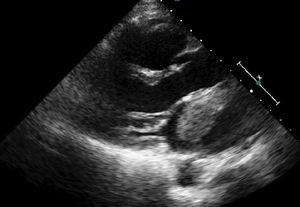

Mujer de 54años, sin factores de riesgo cardiovascular conocidos. Consultó por clínica de disnea de mínimos esfuerzos de una semana de evolución. Además refería pérdida de peso de 7-8kg en los últimos 6meses. En la exploración física se apreciaba un soplo diastólico mitral y edemas en miembros inferiores. En la analítica destacaba una anemia normocítica-normocrómica. Las enzimas cardiacas fueron negativas. Se solicitó dímeroD para descartar tromboembolismo pulmonar, que fue también negativo. El electrocardiograma mostró un ritmo sinusal a 95latidos/min. En la radiografía de tórax no existía cardiomegalia, y se apreciaban hilios congestivos y un patrón intersticial en ambas bases. En el ecocardiograma transtorácico (figs. 1 y 2) se objetivó a nivel de aurícula izquierda una masa homogénea de 47×27mm, móvil y pediculada, con pedículo adherido a tabique interauricular, que prolapsaba hacia la válvula mitral en diástole y provocaba una obstrucción intermitente de la misma, originando una estenosis mitral severa. Con la sospecha de mixoma auricular, se remitió a la paciente de manera urgente al servicio de cirugía cardiaca para extirpación de la masa. A través de una auriculotomía izquierda por vía transeptal superior se procedió a la exéresis del tumor con cauterización de la base de implantación. La anatomía patológica confirmó el diagnóstico de mixoma. La evolución posterior de la paciente fue satisfactoria, siendo dada de alta a los 7días de la intervención. En la revisión a los 6meses la paciente se encuentra asintomática.

La ecocardiografía juega un papel fundamental para poder realizar un diagnóstico precoz en estos pacientes. Nos permite descartar otras entidades que cursan con disnea y soplo, como la miocardiopatía hipertrófica y las valvulopatías. Es importante hacer el diagnóstico diferencial con los trombos intracardiacos, dado la diferente estrategia terapéutica en ambos casos. Como regla general, los trombos suelen aparecer en pacientes con fibrilación auricular, aurícula izquierda dilatada, estenosis o prótesis mitral y tricuspídea, situación de bajo gasto cardiaco y presencia de ecocontraste espontáneo en aurícula izquierda4.